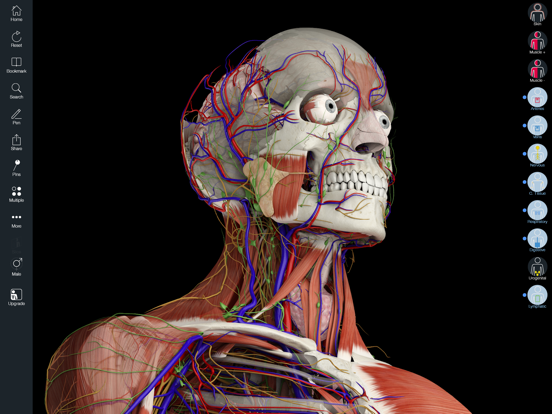

Downloading Essential Anatomy 5 IPA for iOS is a convenient and useful way to explore the world of human anatomy right from the comfort of your iPhone or iPad. This app provides a comprehensive and detailed view of the human body, allowing users to interact with various systems and structures. With stunning 3D graphics, it offers a visually captivating experience that aids in understanding and learning about the complexities of the human body. Whether you are a medical student, healthcare professional, or someone with a general interest in anatomy, Essential Anatomy 5 IPA is a must-have app that provides a wealth of knowledge at your fingertips. The app’s intuitive interface and easy navigation make it accessible to users of all levels of expertise. With just a few taps, you can delve into different layers of the body, explore various organs, muscles, and bones, and gain a deeper understanding of human anatomy. Download Essential Anatomy 5 IPA today and elevate your knowledge and appreciation of the human body.

The Essential Anatomy 5 IPA for iPhone is an incredible tool for medical students, professionals, and anyone interested in learning more about the human body. This app provides a comprehensive and detailed 3D model of the human anatomy, allowing users to explore and study different parts of the body with ease. With its user-friendly interface and interactive features, users can zoom in, rotate, and examine every angle of the human body, from bones and muscles to organs and systems. The app also provides in-depth information about each structure, making it a valuable resource for studying and understanding the intricacies of human anatomy. Whether you’re a medical student preparing for exams or simply curious about the wonders of the human body, the Essential Anatomy 5 IPA for iPhone is an essential tool to have at your fingertips.

Essential Anatomy 5 IPA MOD IOS is a revolutionary app that has changed the way we learn about the human body. With its advanced features and stunning visuals, this app provides an immersive and interactive experience for users. Whether you are a medical student, healthcare professional, or simply interested in learning about anatomy, Essential Anatomy 5 is a must-have tool. It offers a comprehensive library of detailed 3D models, allowing users to explore every aspect of the human body. From the skeletal system to the muscular system, nervous system to cardiovascular system, this app covers it all. Additionally, it provides in-depth information on each structure, including names, functions, and clinical relevance. With its user-friendly interface and intuitive controls, navigating through the app is a breeze. Overall, Essential Anatomy 5 IPA MOD IOS is an essential resource that brings anatomy to life, making it an invaluable tool for anyone interested in the human body.

This app provides a comprehensive and detailed 3D representation of the human body. With over 8,200 anatomical structures, including muscles, bones, organs, and more, it offers a level of accuracy and depth that is unparalleled. Whether you are studying for an exam or explaining a medical condition to a patient, Essential Anatomy 5 IPA has the information you need.

Essential Anatomy 5 IPA allows users to interact with the 3D models, zooming in and rotating them to explore every angle. The user-friendly interface makes navigating through the app a breeze, and the intuitive controls ensure that anyone, regardless of their level of expertise, can easily explore and understand the complex anatomical structures.

One of the standout features of Essential Anatomy 5 IPA is its ability to showcase cross-sectional views of the body. This enables users to see the internal structures and their relationships with each other, providing a deeper understanding of the body’s intricate systems. This feature is particularly useful for students learning about the different body cavities or professionals wanting to explain surgical procedures to their patients.